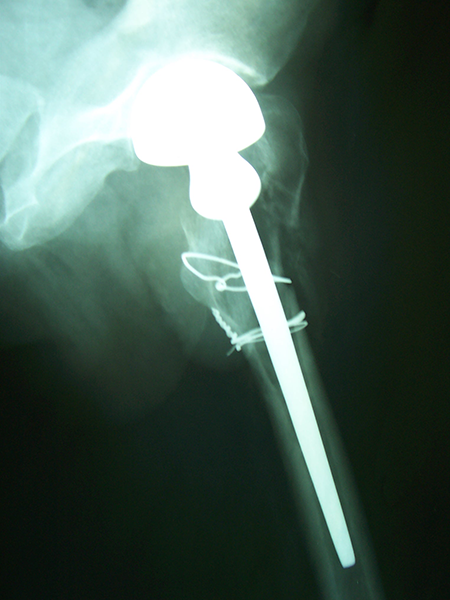

Case:7 Fracture Neck Femur with Implant failure and Re-Fixation with hemi-arthroplasty

Alcoholic Gardener by profession had slipped in bathroom & fell. He sustained fracture neck femur.He was operated with closed reduction & CC Screw fixation under IITV. Two weeks’ post fixation he again fell & sustained fracture in sub trochanteric region. He was treated with Hem-Arthroplasty with Tension band wiring.

Post-Op

Post Fall

Oblique-Post Fall

Lat-Post Fall

Lateral-Post Prosthesis Fall

Post Prosthesis Fall